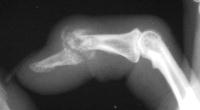

Clinical Example: Distal Interphalangeal Joint Arthroplasty with reversed Ascension carbon implant arthroplasty

These two cases illustrate the use of the Ascension PIP joint implant arthroplasty in the DIP joint position. The stem of the distal component is too wide to fit into the typical distal phalanx, but the proximal component stem will, and in selected cases, the implant will fit in this position if it is placed in a reversed proximal-distal position. These cases illustrate this technique - not as an endorsement, but as a demonstration of  technical feasibility. At one year, each  reconstructed joint was painless and had about 30 degrees range of motion.

Distal interphalangeal erosive osteoarthritis severe enough that the diagnosis of giant cell or other tumor was suspected. Fortunately, no tumor was encountered at surgery.